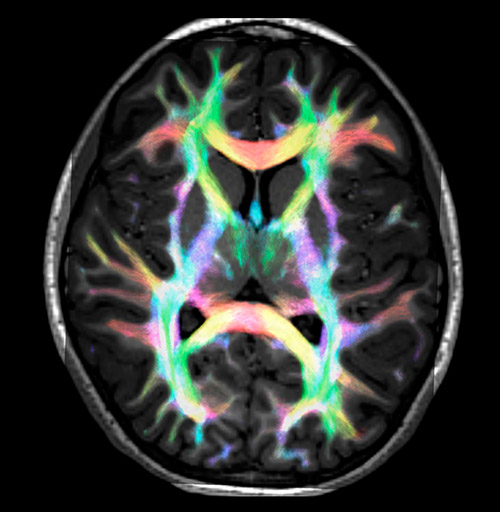

DEC TDI

Super-resolution directionally encoded color track-density imaging overlaid on T1-weighted structural MRI.

Super-resolution directionally encoded color track-density imaging